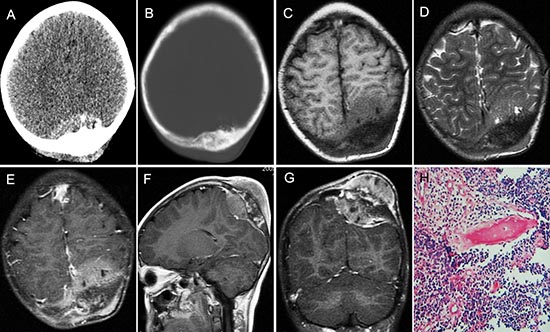

Figure 3: pPNET in an 11-year-old girl. Enhanced CT images showed the left parietal bone had expansive destruction and a fusiform soft tissue mass with enhancement (A and B). Precontrast MRI showed the mass was iso-intense on T1WI (C) and iso-intense on T2WI (D). Contrast MRI showed the mass had significant and heterogeneous enhancement (E). Sagittal (F) and coronal (G) enhanced MRI images showed dural invasion. H&E staining (H × 100) revealed that the tumor tissue consisted of poorly differentiated small round cells.